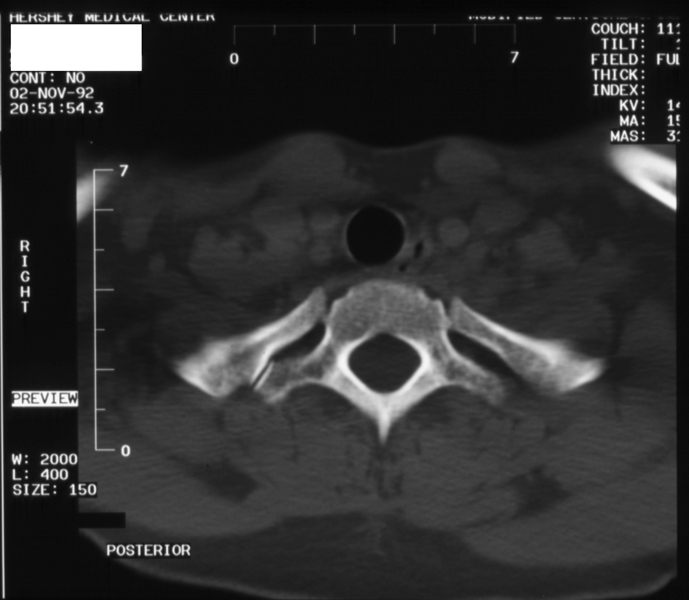

Radiology MS 195 - Normal Thoracic Spine - Axial CT

Identify: vertebral body, pedicile, lamina, spinous process, transverse process, rib, costotransverse joint, spinal canal, trachea